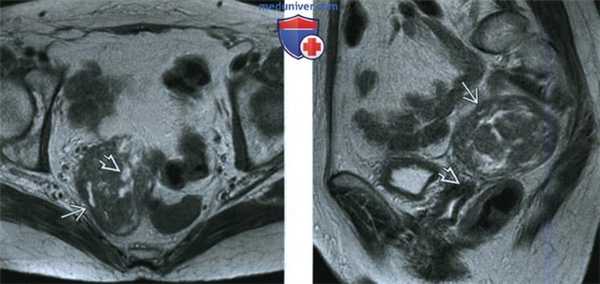

(Слева) При МРТ на Т2-ВИ в аксиальной плоскости у пациентки 62 лет, которой 5 лет назад была выполнена лапароскопическая гистерэктомия в сочетании с двусторонней сальпингоофорэктомией, а незадолго до исследования был диагностирован рак толстой кишки в ранней стадии, выявлено объемное образование в правой половине малого таза. Образование в основном солидное и по сравнению с мышцами таза дает более интенсивный сигнал, обусловленный кистозным компонентом.

(Справа) При МРТ на Т2-ВИ в сагиттальной плоскости у той же пациентки видно объемное образование В в малом тазу, расположенное непосредственно над культей влагалища и не связанное с ней.